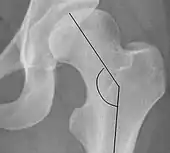

The most useful lines and angles that can be drawn in the pediatric pelvis assessing hip dysplasia are as follows:[3]

- (A) Hilgenreiner line, connects the inferior tips of the iliac bones,[4] at the triradiate cartilage. This line is used to measure the acetabular angle and as a reference for Perkin line.

- (B) Perkin line is perpendicular to Hilgenreiner line, touching the lateral margin of the acetabular roof.[5] This leads to four quadrants and a normal femoral head has to be located in the inferomedial quadrant. We can measure the lateral displacement of the femoral head with regard to the Perkin line by dividing the width of the head that crosses the Perkin line by the diameter of the head. The value for patients under 3 years must be 0 and in older children this ranges from 0 to 22%.

- (C) Shenton line is a continuous arc drawn from the inner edge of the femoral neck to the superior margin of the obturator foramen. In children over about 3 to 4 years of age, this line should be smooth and undisrupted, otherwise it may indicate a fracture or hip dysplasia.[6] However, in infants this line can be unreliable as it depends on the rotation of the hip when the image is taken.[7]

- (D) The acetabular index measures the acetabular roof slope. It is the most useful measure of acetabular dysplasia until 6 years of age. It is formed between Hilgenreiner line and the acetabular roof. In newborns, values of in males and in females are considered normal. It normally decreases with age:

- (E) The medial articular joint space is measured between the medial border of the femoral head or neck (when epiphysis is not ossified) and the acetabular platform. Normal values range between 5 and 12 mm. Differences greater than 1.5 mm between the two sides are considered abnormal.

- Reimer's migration index (MI), also called the femoral extrusion index,[3] is calculated if hip dysplasia is detected. It can be used to indicate hip dislocation. It is the horizontal distance (parallel to the Hilgenreiner Line) between the Perkin line and the lateral border of the ossification center of the femoral head, divided by the horizontal width of the ossification center. The migration index is normally less than 33% by most sources,[9] but 25% and 30% has also been suggested.[10]